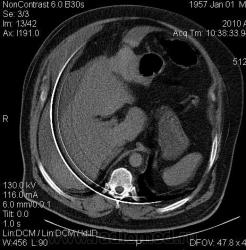

На предмет чего проводилось исследование? Тупая травма живота?

Да. Тупая травма.

Коллега не темните,"Да"-означает тупая травма живота? И что за артефакт на всех сканах?

И сколько тут HU ?

5-9HU

Плотность паренхимы печени = 31-38HU

А почему у морфологов не поинтерисовались? Менее вероятно что в данном случае плотность то, что я отметил 5-6HU, минимум должно быть 50-65HU.

Добавил изображение с замерами.

А тут сколько HU?

Петля 12п.к., вокруг которой жидкость, вообще с учетом анамнеза, я бы сказал о травматическом повреждении паренхимы печени с образованием гематомы вокруг последней и передней стенки брюшной полости, попробуйте архив-dicom залить на файлообменник, чтобы можно было тчательно просмотреть самому.

Вот вам пример бессмысленного исследоваания. Снять сняли, а оценить данные некому. Измерения неверные, так как ROI выставлены на полоски артефактов. Артефакты жуткие, может калибровка давно не проводилась или детекторы полетели.